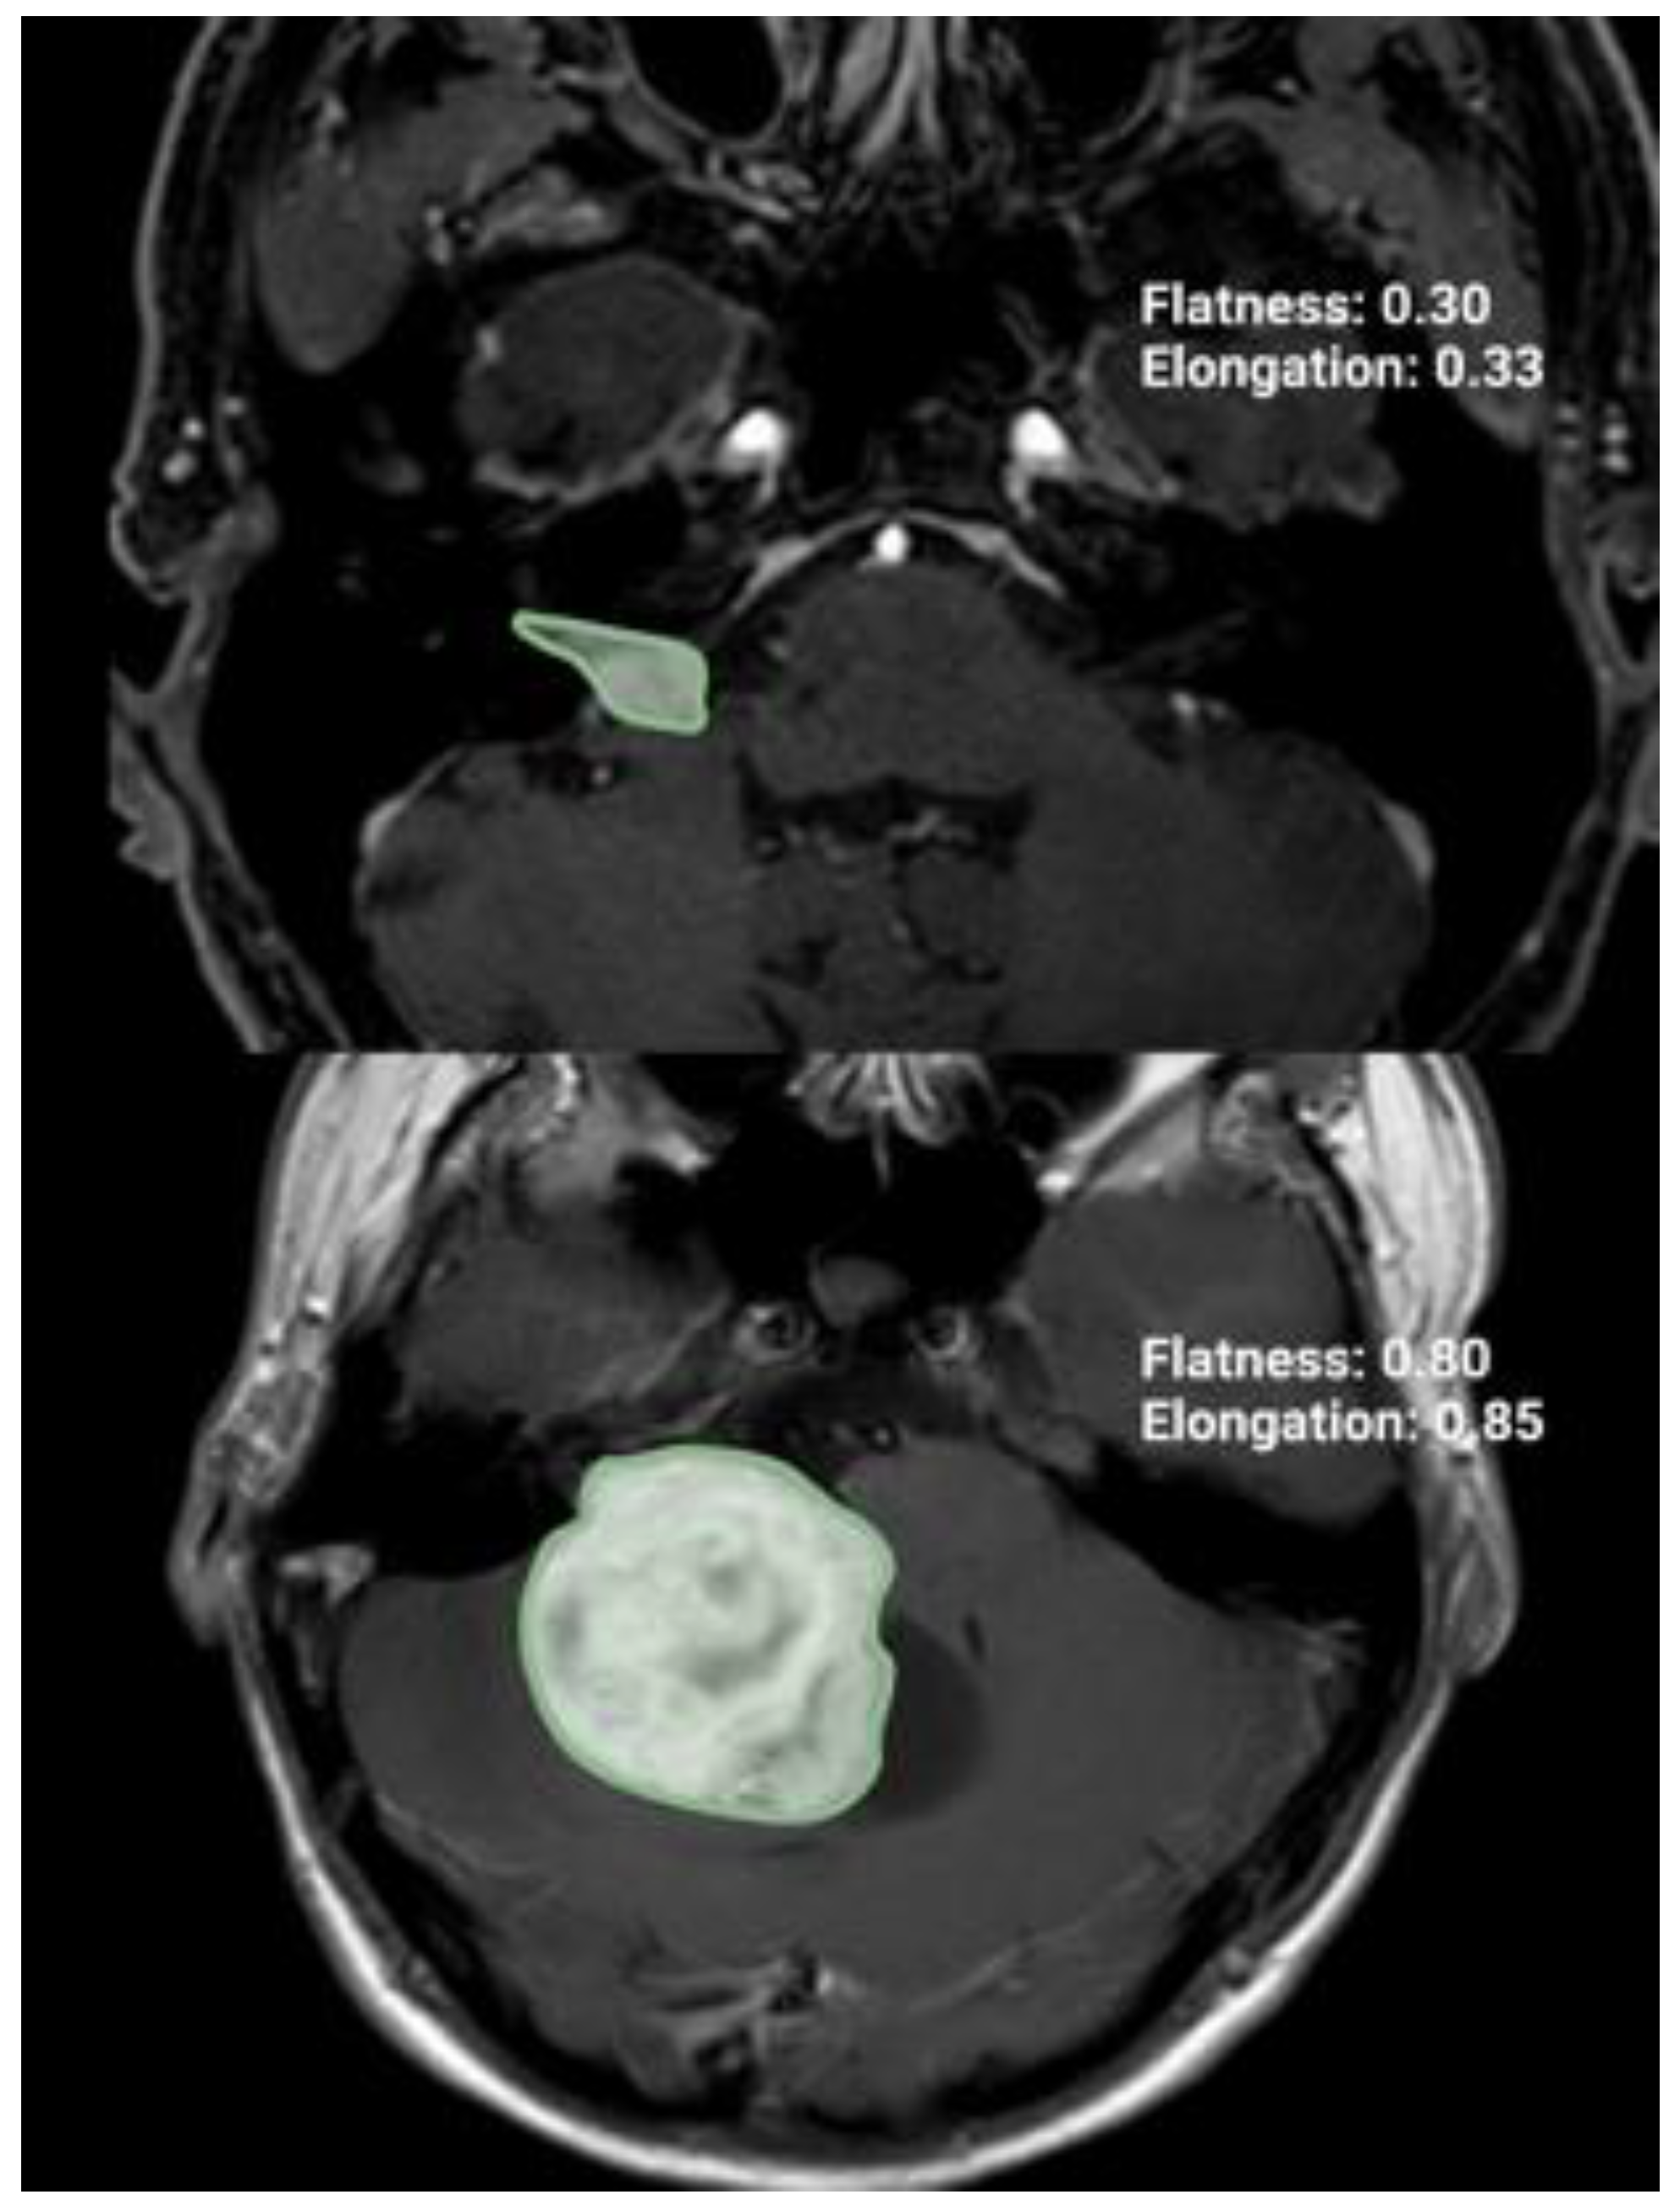

| Flatness | 1.22 ± 0.11 |

| Elongation | 0.46 ± 0.19 |